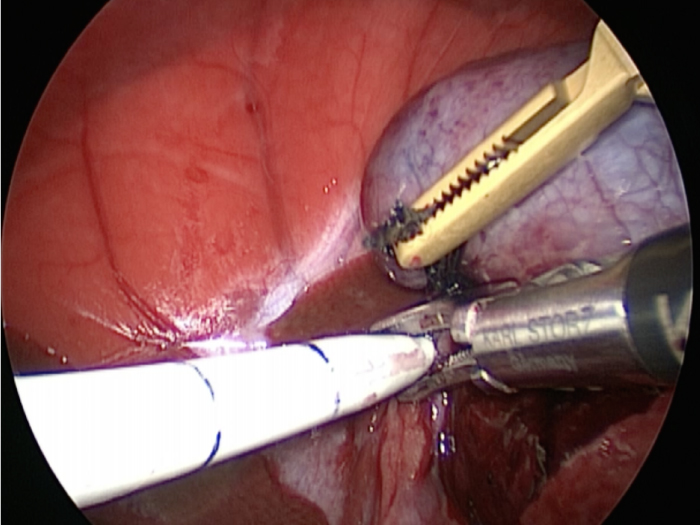

胆嚢の頸部に糸を通し動脈を確保しています。

総胆洗浄をして詰まりがないかまずは確認します。(右)

きれいに開通していました。鉗子が大きく感じますが体が小さいので大きく見えます。

胆嚢を少しずつ丁寧に肝臓から剥がしています。